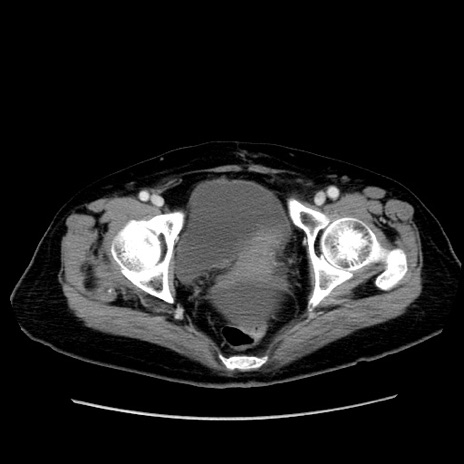

症例19(横断像)

【症例】80歳代女性

【主訴】下腹部痛

【現病歴】約8時間前より下腹部痛の出現あり、救急外来受診。

【既往歴】両側付属器切除

【身体所見】意識清明、下腹部正中に手術痕あり、その部位に一致して圧痛と反跳痛あり。腸蠕動音は亢進。

【データ】WBC 9300、CRP 0.15